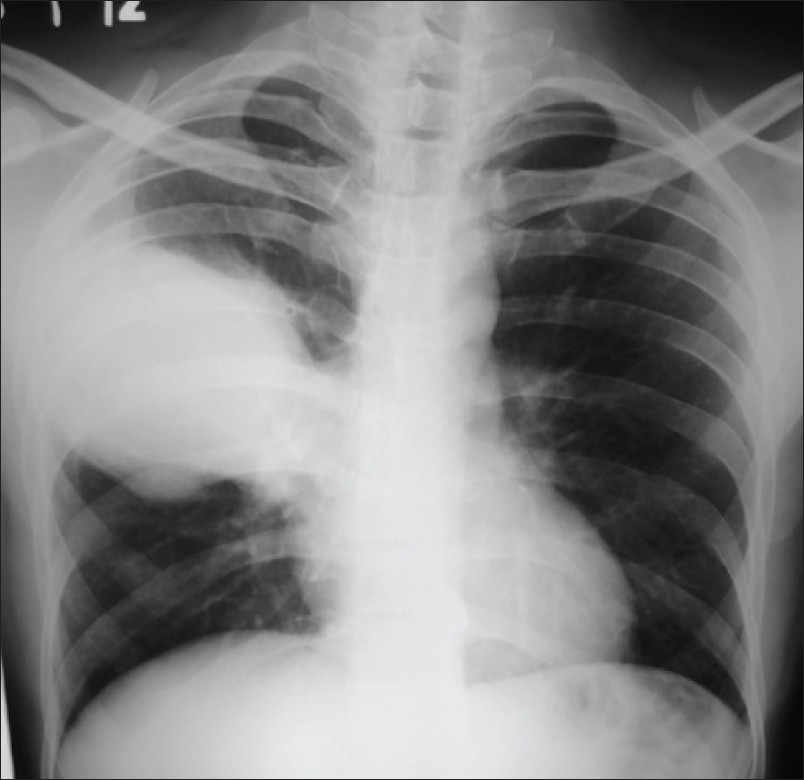

A 37-year-old male came with fever, cough, hemoptysis and chest pain on his right side for last 1 month. He was a chronic smoker and oral tobacco user. He denied any history of tuberculosis or any other chronic illness in the past. On examination his pulse was 100/min, respiratory rate 24/minute and he was afebrile. There was no cyanosis, clubbing or pedal edema. His respiratory system examination was unremarkable except occasional wheezing. HIV was negative and his oxygen saturation was normal. The blood investigations were normal except raised ESR. Pulmonary function tests were suggestive of obstructive airway disease. The chest X-ray revealed a large opacity in the right middle zone [Figure 1]. The closest differential diagnosis initially was made as pneumonia probably of tubercular etiology in view of his prolonged illness and a normal TLC. However, his sputum for AFB and montoux test was negative. A CT scan of the chest was done which revealed a large cavity in the upper lobe with dependent fungal ball in it [Figure 2]. IgG antibodies to Aspergillus were positive in serum. Patient was managed conservatively and started with antifungal drug itraconazole. As he developed massive haemoptysis he had to undergo emergent bronchoscopy for bronchial artery embolization.

Figure 1: X-ray chest: Pulmonary opacity